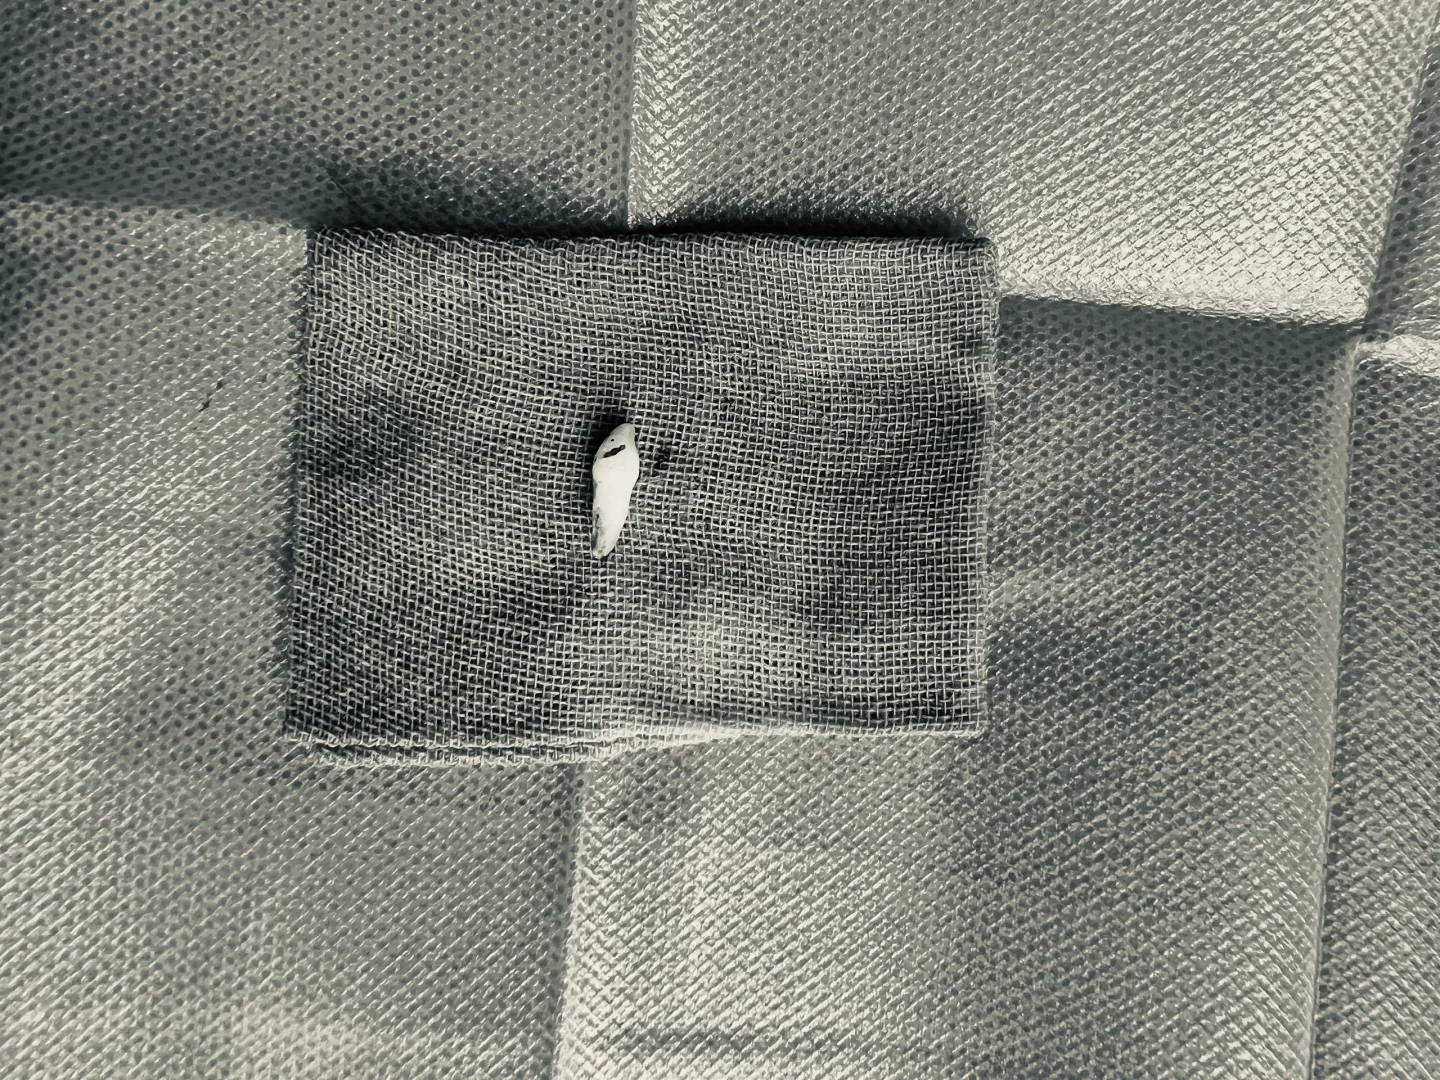

**口腔叫来我们医院口腔科拔掉,再回去矫正,恰好我接了,拍了cbct发现这颗牙倒着长的,牙尖在鼻腔底了,关键无论是唇侧还是腭侧,骨头都很厚,非常难拔!

最后还是选择从腭侧开口进去拔牙,用了差不多一个小时的时间,收了1800块钱,这是我半年来拔的最贵的一颗牙齿🦷了!